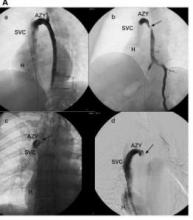

Photo credit: Paolo Zamboni, J. Neurol. Neurosurg. Psychiary 2009;80:392-9

Venography of an open azygous vein in a control individual (A), and a stenosed vein in three MS patients (B, C, D).